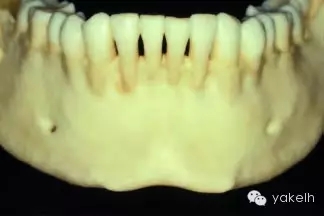

¤¤許多上頜竇以及Onlay植骨的移植物來自于下頜骨頦部。已有報(bào)道從下頜骨前牙區(qū)獲取塊狀骨以及顆粒狀骨的技術(shù)。頦部是口內(nèi)能提供最大骨量的區(qū)域(圖13.15)。兩頦孔間的平均距離為5cm,平均厚度為1cm。CT掃描以及全景片能夠評(píng)估該區(qū)的可供骨量。頭影測(cè)量片可測(cè)定下頜骨前牙區(qū)的前后徑。根尖片能更精確地測(cè)量牙根長(zhǎng)度。

圖13.15 干燥的標(biāo)本提示,從下頜骨頦部可以獲取大量的骨質(zhì)。